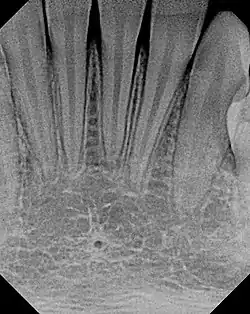

The small lingual foramen (black "hole" in lower portion of picture) as seen on a periapical radiograph of the anterior mandible.

The lingual foramen is a small midline opening on the posterior aspect of the symphysis of the mandible, just above the mental spine. The lingual foramen gives passage to a single small artery formed by the union of two branches of the sublingual arteries (each sublingual artery contributing a single branch).[1]